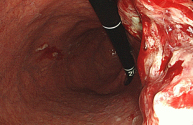

정상 위의 내시경 사진

식도암